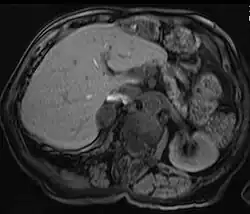

Diagnosis

Due to their asymptomatic nature, most reported cases of adrenal adenomas have been discerned fortuitously through autopsy, or during medical imaging, particularly CT scan (computed tomography) and magnetic resonance imaging. Hence, they have earned the title incidentaloma referring to small adenoma discovered incidentally.[9] Though adrenocortical adenomas are considered challenging to differentiate from the normal adrenal cortex, they appear as well-circumscribed lesions once isolated.

Imaging Diagnostics

Adrenal-dedicated CT and MRI imaging can be performed to distinguish benign adenomas from potentially malignant lesions.[10] Online calculators assist radiologists in calculating the washout of contrast in adrenal nodules on CT[11] and chemical shift on MRI[12].